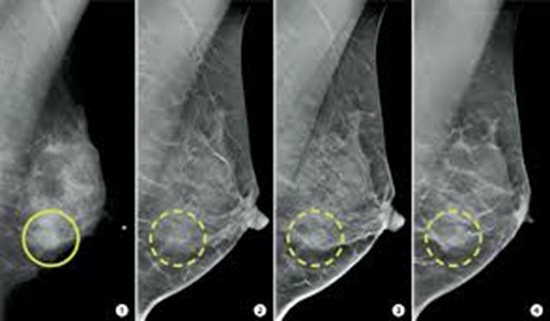

ارزش افزوده توموسنتز(ماموگرافی دیجیتال سه بعدی) به ماموگرافی دیجیتال تمام دیژیتال در تصویربرداری پستان. یک مطالعه مقطعی کد خبر : 293219 کپی کلمات کلیدی ماموگرافی_دیجیتالتوموسنتزتصویربرداری_پستان